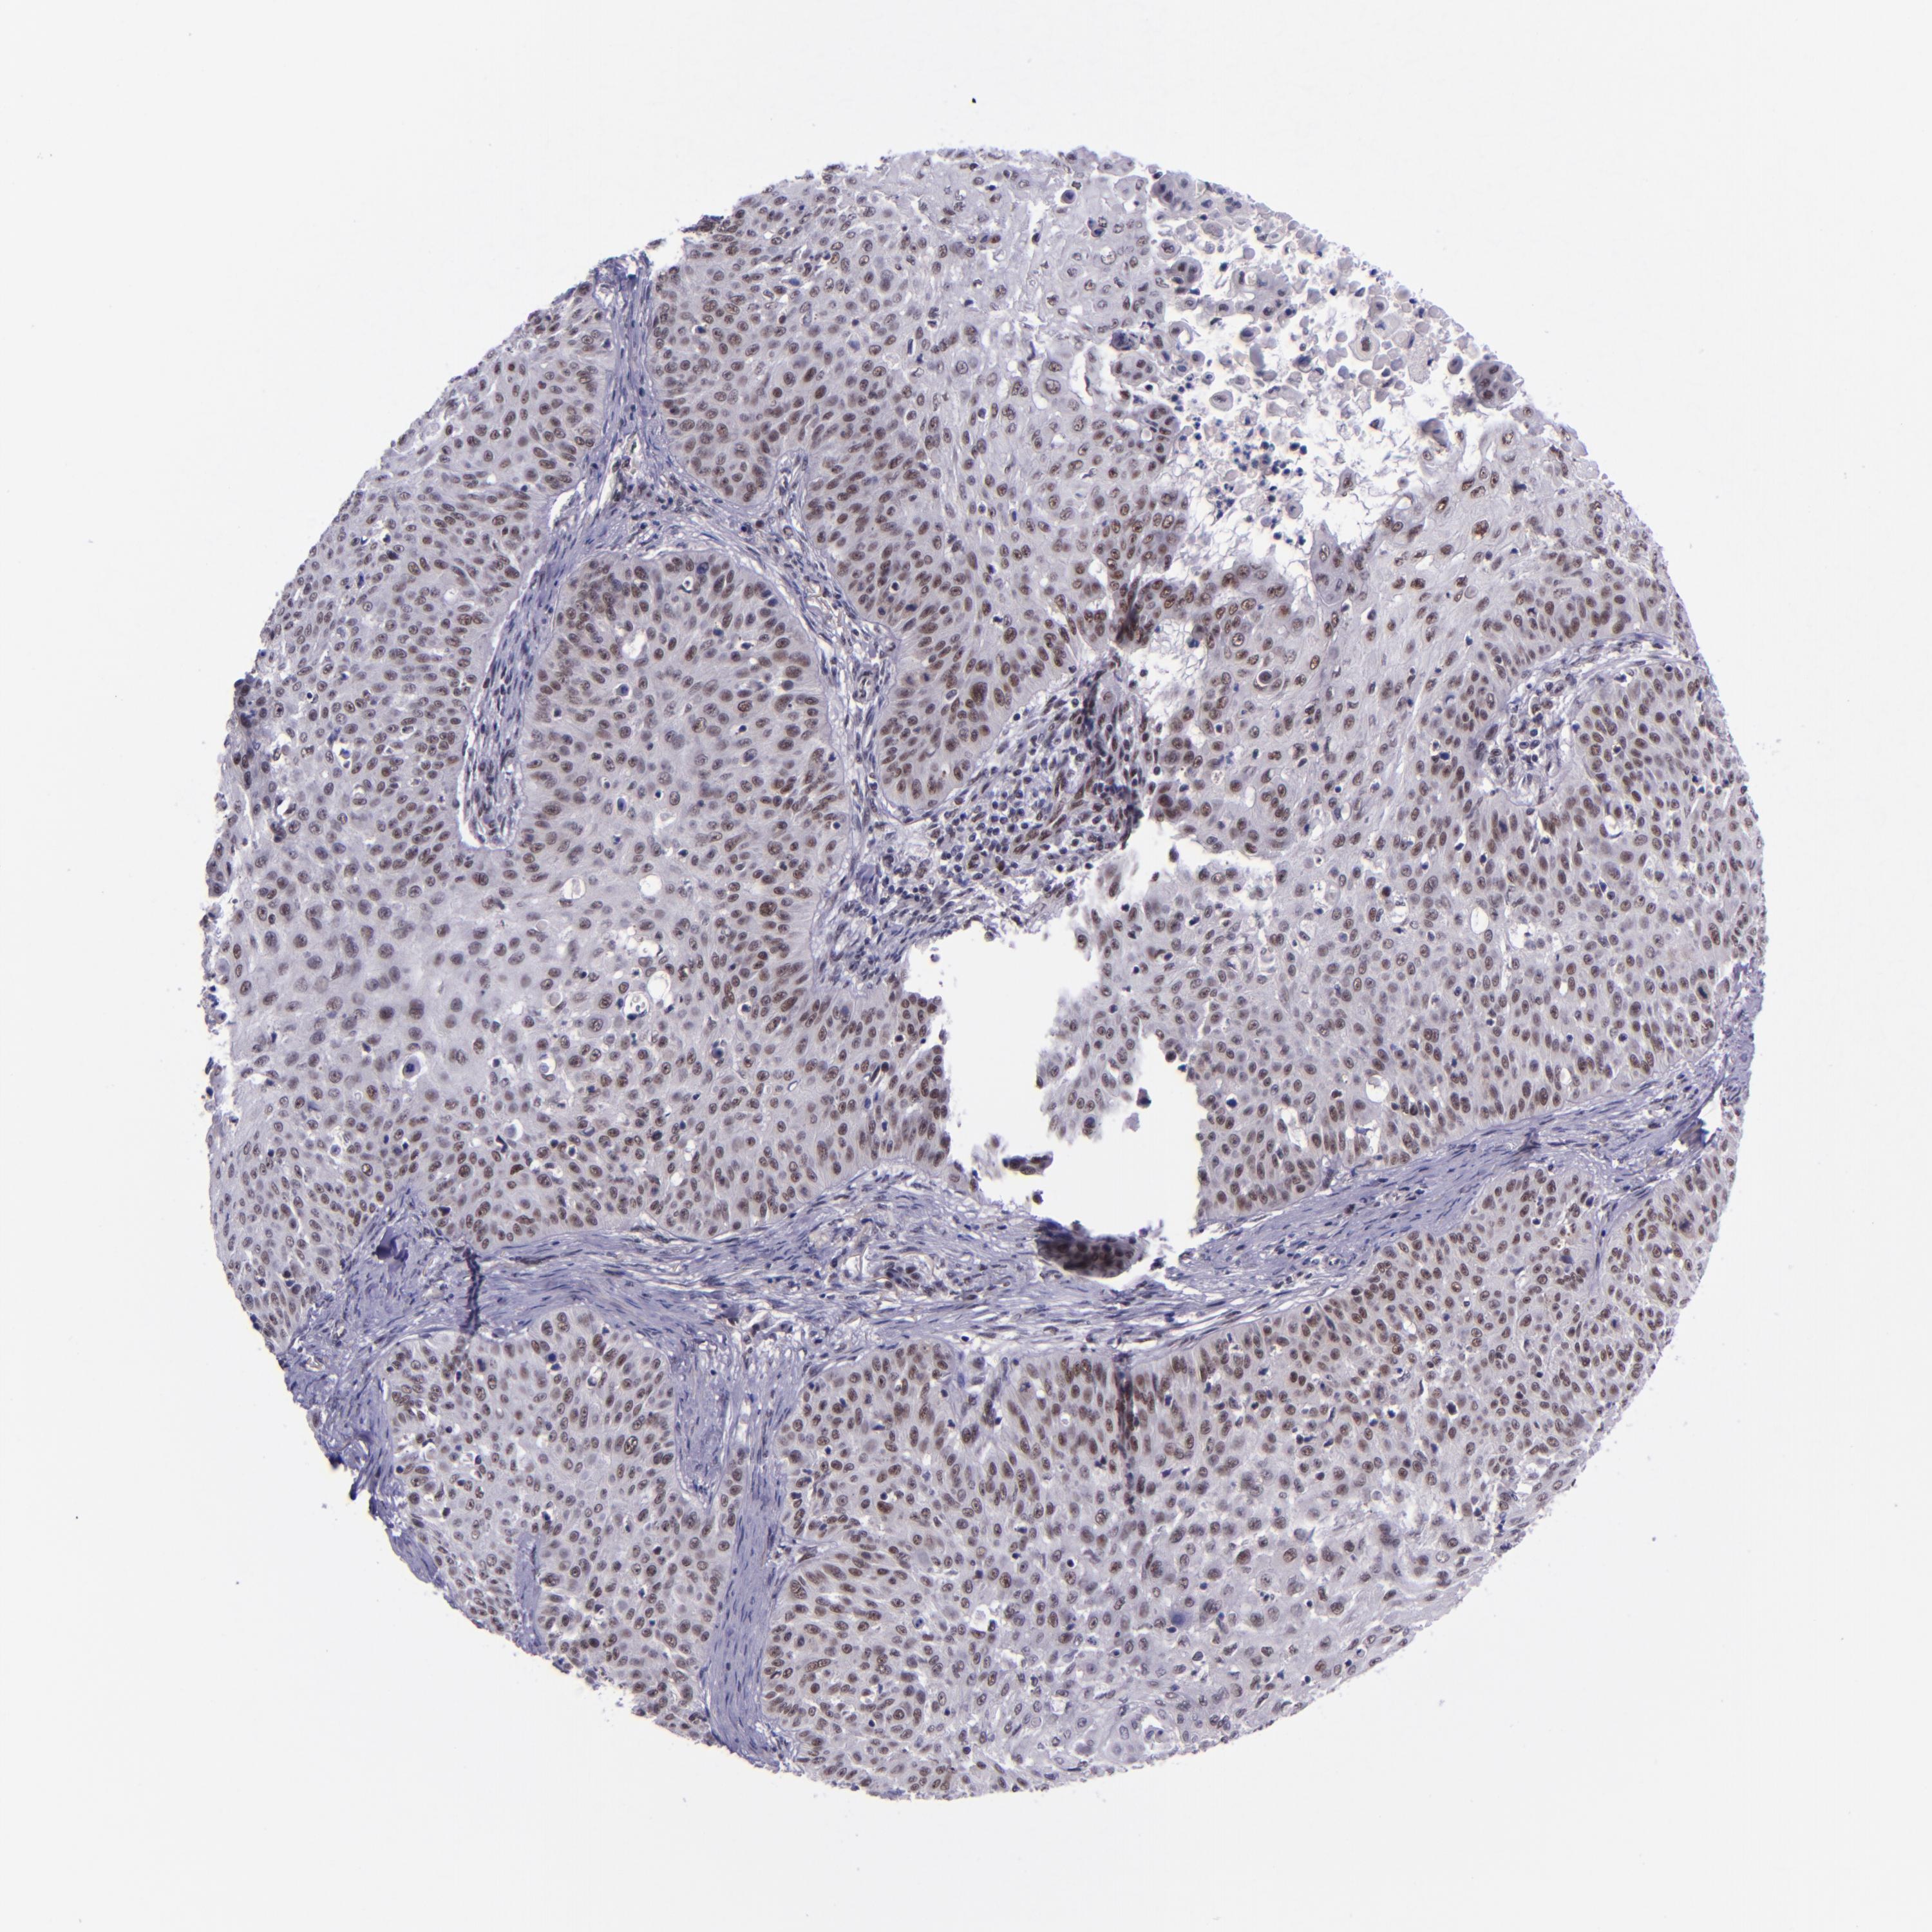

SKIN CANCER - Protein expressioni

A mouse-over function shows sample information and annotation data. Click on an image to view it in a full screen mode. Samples can be filtered based on level of antibody staining by selecting one or several of the following categories: high, medium, low and not detected. The assay and annotation is described here.

Antibody stainingi

Antibody staining in the annotated cell types in the current human tissue is reported as not detected, low, medium, or high, based on conventional immunohistochemistry profiling in selected tissues. This score is based on the combination of the staining intensity and fraction of stained cells.

Each image is clickable and will lead to virtual microscopy that enables deeper exploration of all samples and also displays staining intensity scores, fraction scores and subcellular localization as well as patient and tissue information for each sample.

Antibody HPA000287

Antibody HPA001894

Staining

High

Medium

Low

Not detected

Intensity

Strong

Moderate

Weak

Negative

Quantity

>75%

75%-25%

<25%

None

Location

Nuclear

Cytoplasmic/membranous

Cytoplasmic/membranous,nuclear

Squamous cell carcinoma, NOS

Basal cell carcinoma